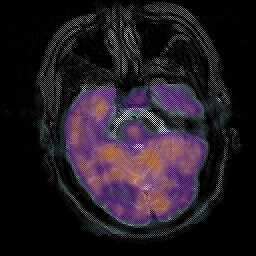

Subacute Stroke, overlay -- Slice #7

[Home][Help][Clinical] Slice 7